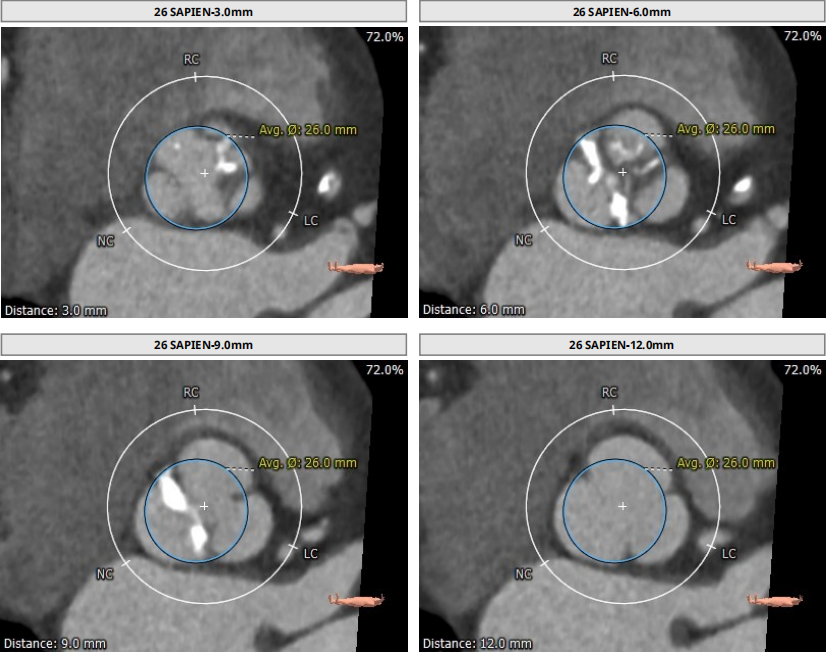

术前CT结果显示:主动脉瓣口面积473.6mm²,瓣环平均直径24.7mm,瓣环周长78.1mm;LVOT面积448.7mm²,LVOT平均直径24.1mm;左冠开口高度14.5mm、右冠开口高度16.2mm。

术前CT检查结果

考虑到患者再发冠脉狭窄机率可能较高,综合各项报告,并且与外院专家充分讨论后,手术团队最终决定采用23mm预扩球囊和26mm SAPIEN 3瓣膜减少1CC体积释放。

瓣膜选择软件分析报告